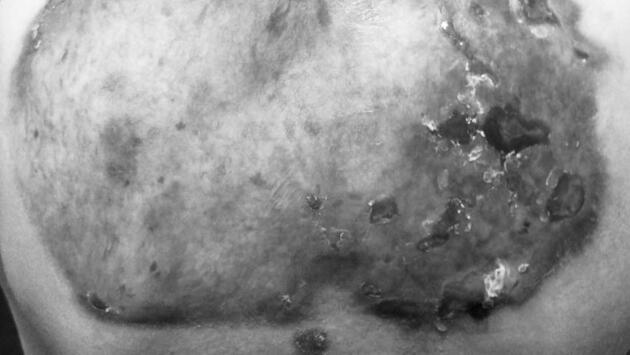

Болезнь генетическая и крайне опасная для носителя. Даже слабое механическое воздействие может привести к образованию пузырей на различных областях кожного покрова, а далее образовываются рубцы на месте поражения. Порой это происходит и без какого-либо воздействия, непроизвольно. Рязанские пациент с таким диагнозом с младенчества.

Всего в России детей с подобным диагнозом 494, а в Рязани будут применять лечение впервые. В частности, в медучреждение доставят препарат «Виджувек» для локальной генной терапии ран.